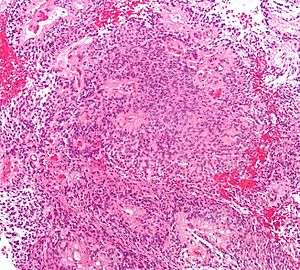

| Micrograph of an ependymoma. H&E stain. | |

Ependymomas are composed of cells with regular, round to oval nuclei. There is a variably dense fibrillary background. Tumor cells may form gland-like round or elongated structures that resemble the embryologic ependymal canal, with long, delicate processes extending into the lumen; more frequently present are perivascular pseudorosettes in which tumor cells are arranged around vessels with an intervening zone consisting of thin ependymal processes directed toward the wall of the vessel.[2]

It has been suggested that ependymomas are derived from radial glia.[3]